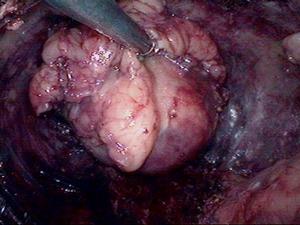

沿皮紋切開脂肪瘤的表麵皮膚。用彎止血鉗沿瘤體包膜分離腫瘤,鉗夾及結紮所有見到的血管。脂肪瘤多呈多葉狀,形態不規則,應注意完整地分離出 具有包膜的脂肪瘤組織。用組織鉗提起瘤體分離基底,切除腫瘤。止血後,分層縫合切口。

沿皮紋切開脂肪瘤的表麵皮膚。用彎止血鉗沿瘤體包膜分離腫瘤,鉗夾及結紮所有見到的血管;脂肪瘤多呈多葉狀,形態不規則,應注意完整地分離出 具有包膜的脂肪瘤組織。用組織鉗提起瘤體分離基底,切除腫瘤;